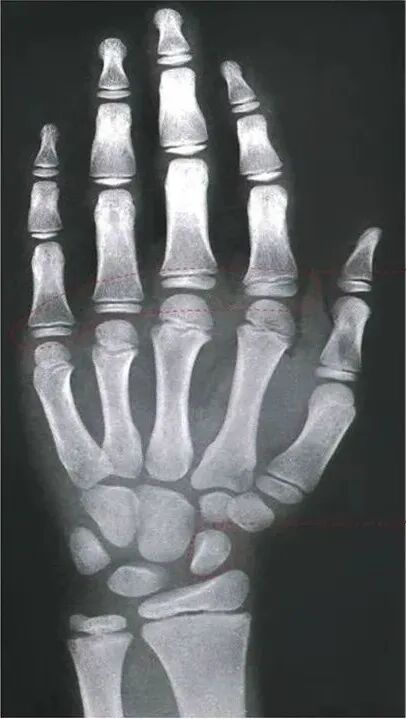

核心标准:骨龄检测,拍左手腕骨X光片查看骨骺状态